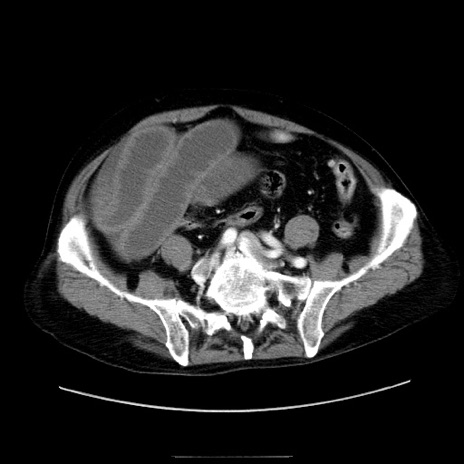

症例30(横断像)

【症例】80歳代男性

【主訴】臍周囲痛

【現病歴】約6時間前から臍下部痛が出現。次第に腹部膨隆・背部痛も生じてきたため来院。背部痛の場所は変化しない。

【既往歴】腎盂腎炎

【身体所見】意識清明、BT 36.3℃、BP  131/87mmHg、P 87bpm、SpO2 100%(RA)、臍周囲自発痛・圧痛あり、反跳痛なし、自発痛部位に一致して板状硬あり、腹部膨隆、腸雑音減弱、CVA tenderness両側陰性。

【データ】WBC 19600、CRP 0.33